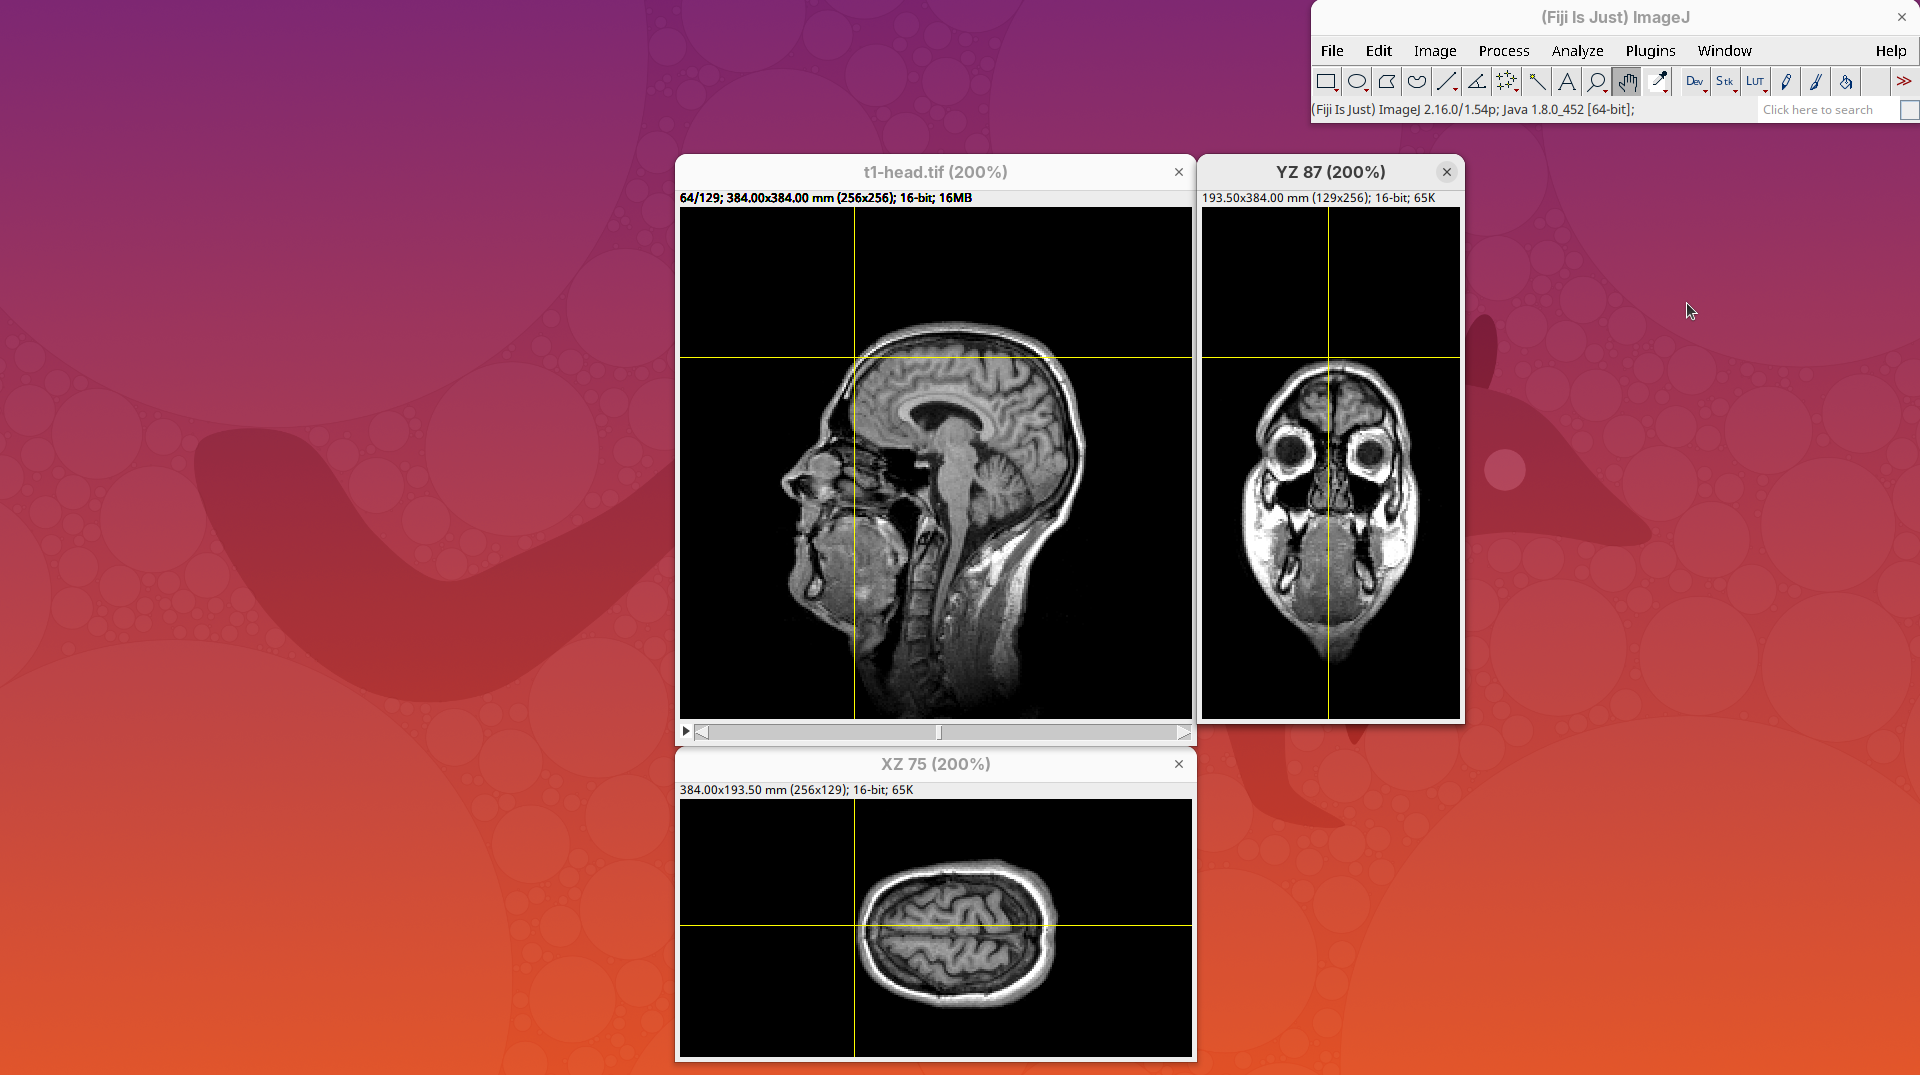

BigDataViewer

BigDataViewer (Pietzsch et al. 2015) is one of the most important tools for visualizing large, multidimensional datasets. It provides a simple and intuitive interface and shortcuts to swiftly navigate through your sample even on a regular laptop. This is possible because of the underlying file format used by BigDataViewer: the XML/HDF5 combo. Therefore, before opening the plugin, we must convert our dataset.

The XML file stores metadata information about the image. The HDF5 file stores actual image data. These two files will always be in a pair. To open the XML/HDF5:

- Go to

Plugins>BigDataViewer>Open XML/HDF5and select thet1-head.xml.

The BigDataViewer interface will open showing an optical section of the head sample.

Getting familiar with BigDataViewer is an essential skill for navigating large 3D datasets. It’ll also be important for the multiview registration pipeline. So, take the time to learn the basic commands and shortcuts. It is nicely intuitive. The BigDataViewer’s page on the ImageJ Docs has the official documentation and we can also go to Help > Show Help for an up-to-date overview.